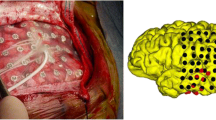

Intracranial EEG

If confident localization of the EZ has not been achieved after non-invasive evaluation, intracranial EEG recording maybe considered if there is a reasonable hypothesis. These often include patients with normal MRI or even lesional cases with discordant data or proximity to eloquent cortex. Subdural (Fig. 4) or depth electrodes are surgically implanted and sVEEG performed to capture inter-ictal / ictal recording from the cortex to exactly delineate the EZ as well as accurately map eloquent areas. Then a second stage resection is carried out.